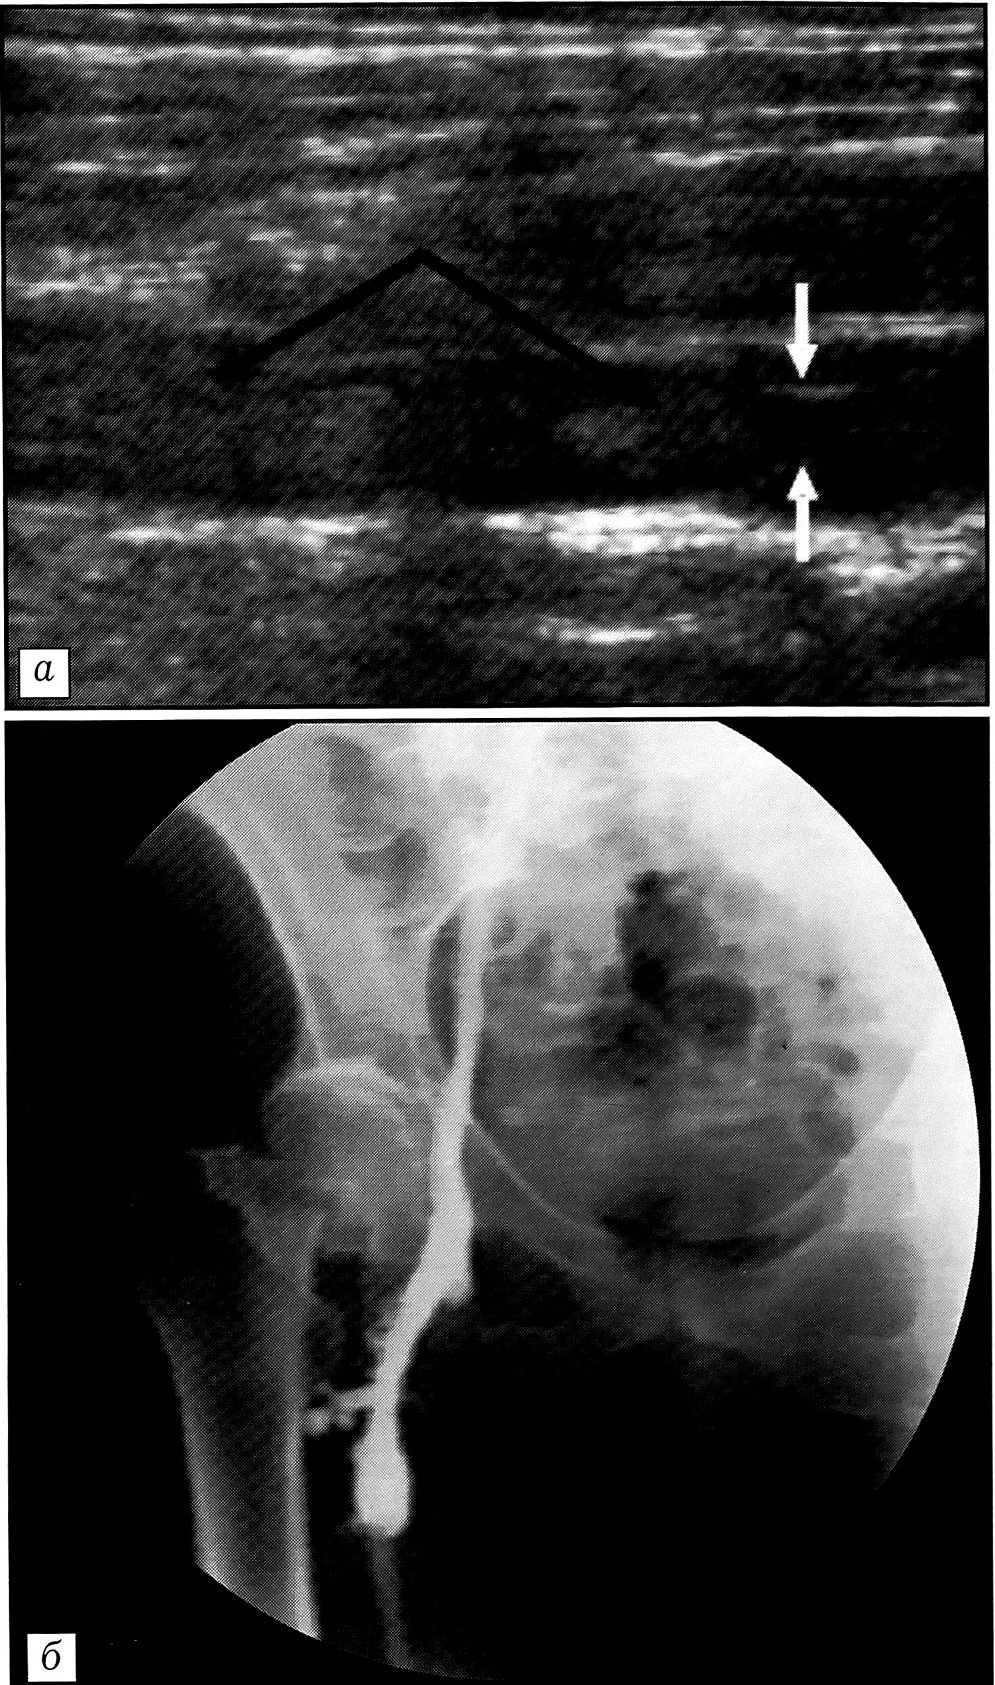

Из 4 больных, у которых был диагностирован дистальный ТГВ, у 3 выявлена окклюзия одной из задних большеберцовых вен в средней трети. При ультразвуковом ангиосканировании эта патология обнаружена в двух случаях, в одном случае диагноз поставлен только после дистальной флебографии. У одного больного выявлена окклюзия малой берцовой вены с флотирующей верхушкой тромба в подколенной вене (рис. 4, а). В этом случае данные ультразвукового ангиосканирования и дистальной флебографии совпали.

Больным с подтвержденным диагнозом дистального ТГВ проводилась антикоагулянтная терапия низкомолекулярным гепарином в лечебных дозах с положительным эффектом: при динамическом наблюдении ультразвуковые признаки нарастания тромбоза отсутствовали. При контрольном ультразвуковом ангиосканировании через 2 мес у пациента с верхушкой тромба в подколенной вене отмечены восстановление кровотока в ней (рис. 4, б) и лизис тромба.

Рис. 4. Ультрасонограммы больного с дистальным тромбозом глубоких вен.a — в ближайшем периоде после эндопротезирования тазобедренного сустава: верхушка флотирующего тромба (стрелка) в подколенной вене; б — ультрасонограмма с цветовым кодированием кровотока в подколенной вене через 2 мес после выявления ТГВ: полное восстановление кровотока.